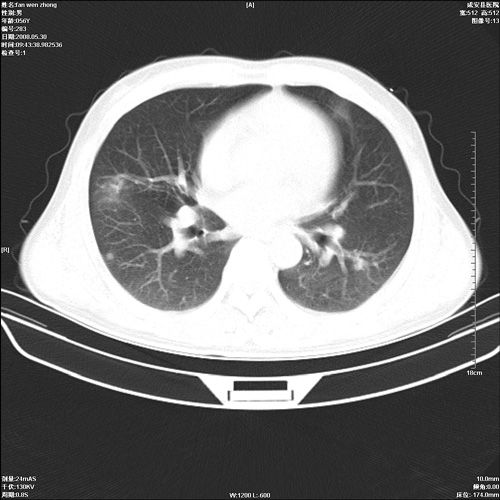

病人 男 56岁 一周前高热,体温达39-40度,经抗炎治疗后,体温渐降,达37,5-38度,轻微咳嗽,胸部不适 查白细胞为1.3万 行ct检查,请分析。

双肺内可见多发结节状病灶,并见小空洞,病人高热,白血球增高,应该是典型的迁徙性肺脓肿(多为金黄色葡萄球菌感染)。查一下口腔等其它部位有无感染灶。

双肺内可见多发结节状病灶,并见小空洞,病人高热,白血球增高,应该是典型的迁徙性肺脓肿(多为金黄色葡萄球菌感染)。建议治疗后复查.